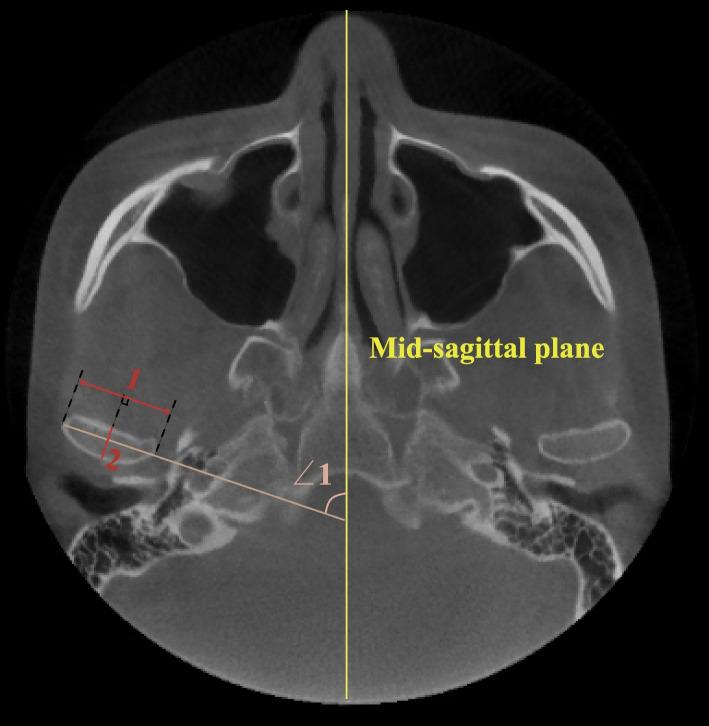

A total of 117 skeletal class II patients were divided into three groups according to the FH-GoGn angle (hypodivergent, normodivergent and hyperdivergent), with 40 class I normodivergent patients serving as controls. Each group contained two age subgroups (adolescents: 11-14 years old, adults: 18-35 years old). The size (condylar length, height, long and short axis diameter, glenoid fossa width and depth) and shape (condylar neck inclination, condylar head angle and long axis angle, articular eminence inclination) of the condyle and fossa, joint space (anterior, superior, posterior, mesial and lateral), and position of the fossa (vertical, transverse, and anteroposterior distance) and condyle were measured and compared using CBCT.

共纳入 117 例骨性 II 类患者,根据 FH-GoGn 角(低角、均角和高角)分为三组,其中 40 例 I 类均角患者作为对照组。每组分为青少年组(11-14 岁)和成年组(18-35 岁)。使用 CBCT 测量并比较髁突的大小(髁突长度、高度、长轴和短轴直径、关节窝宽度和深度)和形态(髁突颈倾斜度、髁突头部角度和长轴角度、关节结节倾斜度)、关节间隙(前、上、后、内、外侧)和关节窝位置(垂直、横向和前后距离)及髁突位置。